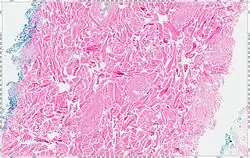

A low power of a nuchal-type fibroma showing entrapped fat.

The tumors are unencapsulated and poorly circumscribed, showing a firm, white cut surface. Most tumors are about 3.5 cm, but can be up to 8 cm.[1] By microscopic examination, there are haphazardly arranged thick collagen fibers, with a low cellularity and no pleomorphism. There are usually entrapped fat cells, skeletal muscle, and peripheral nerves. The may be perineural fibrosis. The elastic fibers may be altered, which is why an elastofibroma is considered in the differential diagnosis.[1]